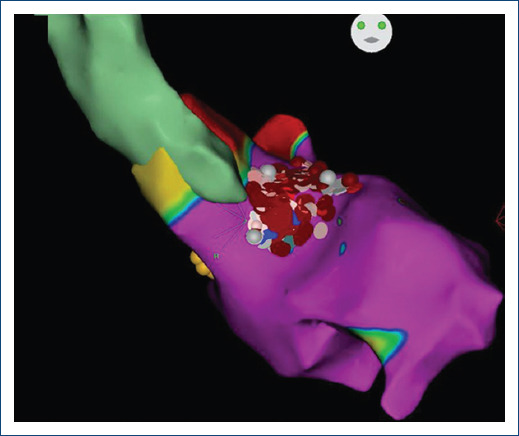

Endocardial radiofrequency ablation of septal hypertrophy: a four-year follow-up case report.